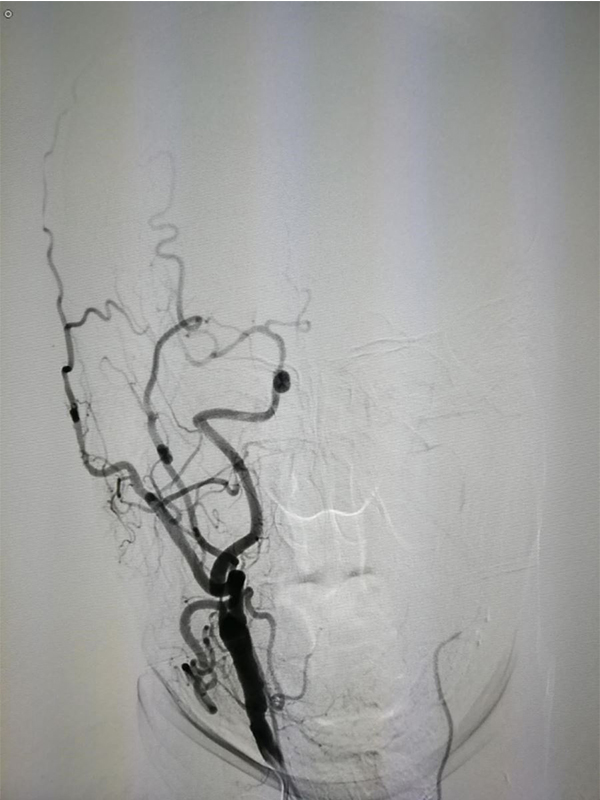

MRA CTA (CT ) DSA <50 %) MRA 50 % CTA 80% DSA 99 % ( ) CTA DSA

CTA 100 % 63 %(95 % 25 %-88 %) 70 % 100 %